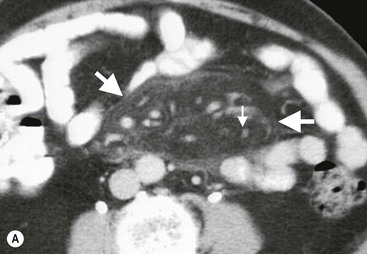

Common findings include the combination of free or loculated ascites, thickened strands with crowded vascular bundles within mesentery, smooth uniform thickening of the peritoneum and a smudged pattern of omental involvement infiltrated by small ill-defined soft tissue (Fig. 30-5).9 On CT, high-attenuation ascites (20–45 HU), reflecting its high protein content, may be seen. Lymphadenopathy is a common manifestation of abdominal tuberculosis and mesenteric nodes are frequently affected.

Peripheral enhancement with central low attenuation on CT may be seen and corresponds histologically to peripheral highly vascular inflammatory reaction around central liquefaction or caseous necrosis.10 This appearance is suggestive but not pathognomonic of tuberculosis as low-attenuation mesenteric lymph nodes may also be seen with Whipple's disease, necrotic metastases, infection with Mycobacterium avium-intracellulare, the cavitating mesenteric lymph node syndrome of coeliac disease and occasionally lymphoma.11